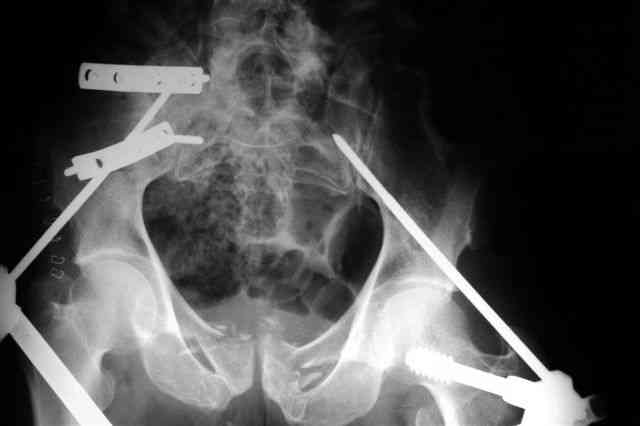

Я помню технику транссакральной фиксации тазового кольца длинными 5 мм Шанцами - повреждения типа В, в этом же случае задний отдел тоже вовлечен

т.е комбинированная нестабильность, поэтому вопрос - достаточно ли только двух Шанцев для стабилизации таза? Что вы думаете об anterior Right SI joint plating + tension band plating from the back.?

PS после фиксации бедра под Эопом посмотрел инлет и аутлет проекции, насколько репонируемо смещение правой половины таза *невооруженными*

руками - никаких шансов улучшить позицию иначе бы конечно воспользовался длинными Шанцами сразу после бедра.